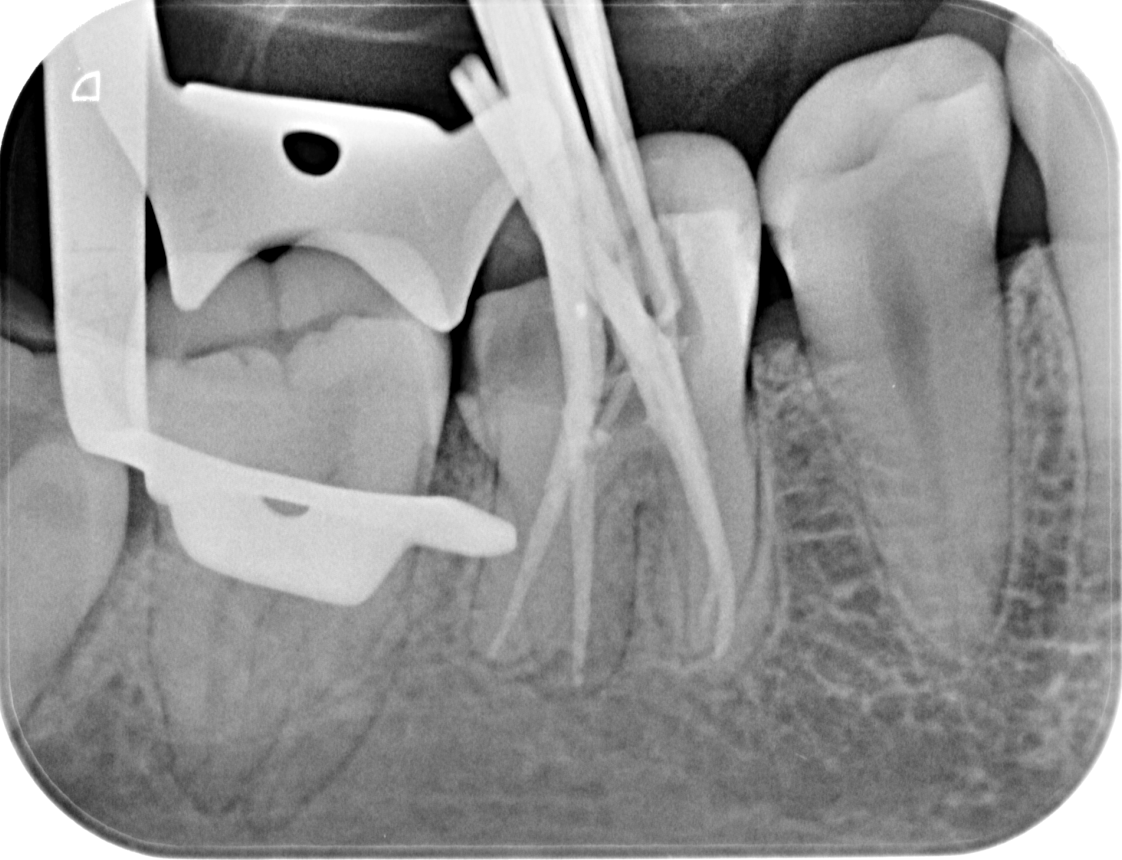

Every procedure is performed under magnification with a rubber dam in place. Electronic length measurement (apex locator) ensures accuracy to the tip of the root. - Thorough cleaning and reliable sealing

We examine the tooth, test its response, and take focused images. When roots are complex or a previous treatment failed, a small 3D scan may be needed for mapping before we discuss and agree on the plan. - Anaesthesia and comfort

Under bright magnified light, a tiny opening is created and every canal located — even the hidden ones that often cause failures elsewhere. - Cleaning and shaping

The canals are shaped with flexible rotary files to create an ideal form for irrigation while preserving tooth strength. - Disinfection